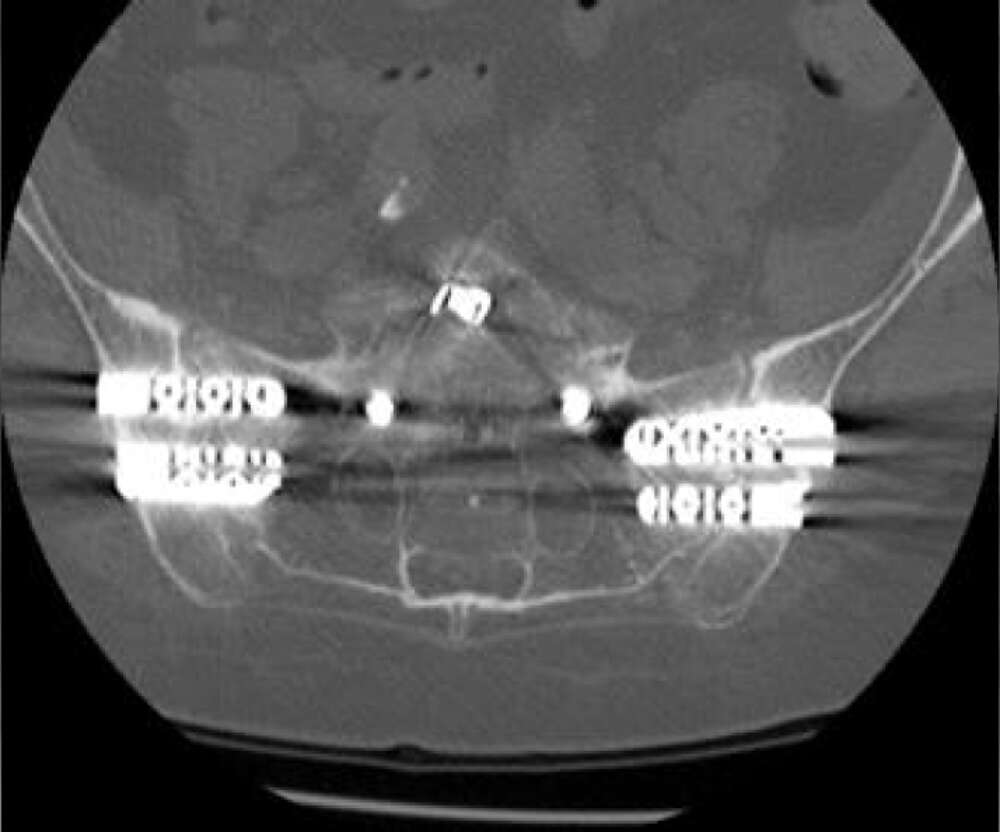

- Bilateral SI joint fusion using the iFuse 3D™ Implant System, August 2020

- Post-op resolution of bilateral SI joint pain.

- CT of lumbar spine at +2 years post-op shows confirmation of the SI joint fusion.

Inline dennis 03